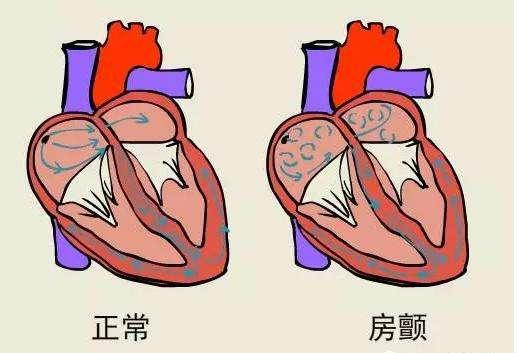

脳梗塞の原因としては、よく耳にする心房細動もあるが、心房内に塞栓ができると、それが外れて脳梗塞になることがある。したがって、心房細動も脳梗塞の重要な原因である。もちろん、心房細動による脳梗塞と脳動脈硬化症や脳血栓症による脳梗塞とは病態基盤が全く異なるので、通常の治療法も異なり、抗血小板療法を強化する場合と、抗凝固療法に注意する場合とがある。

4、一目で答えの比較は、ここで少し拡大するように、脳塞栓症は、多くの場合、心機能の問題を伴っている、臨床我々は、脳塞栓症患者は、多くの場合、心房細動を伴うことがわかった、この異常な心拍パターンは、多くの場合、脳塞栓症をもたらす脳に到達する体の血液循環で、血栓オフの心臓の壁に取り付けられている。

5、心房細動患者に対して、我々は積極的に心房細動による害を予防しなければならない、心房細動患者の脳血管リスクは普通の人より約60%高い、どのように心房細動に介入するか、古い治療方法であるワルファリン薬の使用(弊害は出血のリスクが増加することで、定期的に病院に行って凝固機能を見直す)、現在では新しいタイプの抗凝固薬(例えば:ダビガトランやリバロキサバンドロン薬)を使用する傾向があり、安全性ははるかに優れています。現在では、より安全性の高い新しい抗凝固薬(例えば、ダビガトランやリバロキサバンドロン)が使用されることが多くなっています。

脳塞栓症を心臓性脳塞栓症と呼ぶ人もいるが、これは脳塞栓症の一般的な原因が心臓にあり、心臓の異常病変が塞栓を生じやすいことを示している。心房細動、リウマチ性心疾患、急性心筋梗塞、人工心臓弁などである。

また、不整脈の心房細動によってできる血栓もある。正常な心臓では、拍動のたびに心臓内の血液がすべて送り出され、心臓内に血液が残留することはない。しかし、心房細動が起こると、血流の一部が心臓内に滞留し、血液が長時間滞留すると、血液が固まって血栓(血の塊)を形成する。そして、この血栓が血管とともに脳血管に流れ込み、脳血管を閉塞して脳梗塞を引き起こす。このような脳梗塞を防ぐには、心房細動が発見されたら、抗凝固療法、心房細動を治す手術、左耳の閉塞など、どのようなものであっても、専門医を見つけ、専門的な治療を受け、正式に治療することである。